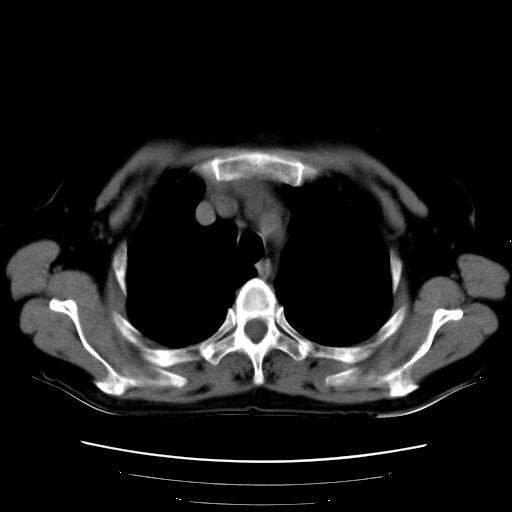

以下是引用卜一在2007-9-18 14:41:00的发言:[br]右肺肿块:毛刺+胸膜凹陷征+供血血管+浅分叶+强化。支持:周围性肺癌 !另:左侧甲状腺腺瘤!

以下是引用夏季在2007-9-18 11:00:00的发言:[br]1。右肺肿块,周围有短毛刺,肺门侧有血管与其相连,胸壁侧有胸膜凹陷征,考虑周围性肺癌 2。左侧甲状腺软组织肿块,内有高密度钙化灶,考虑左侧甲状腺腺瘤。